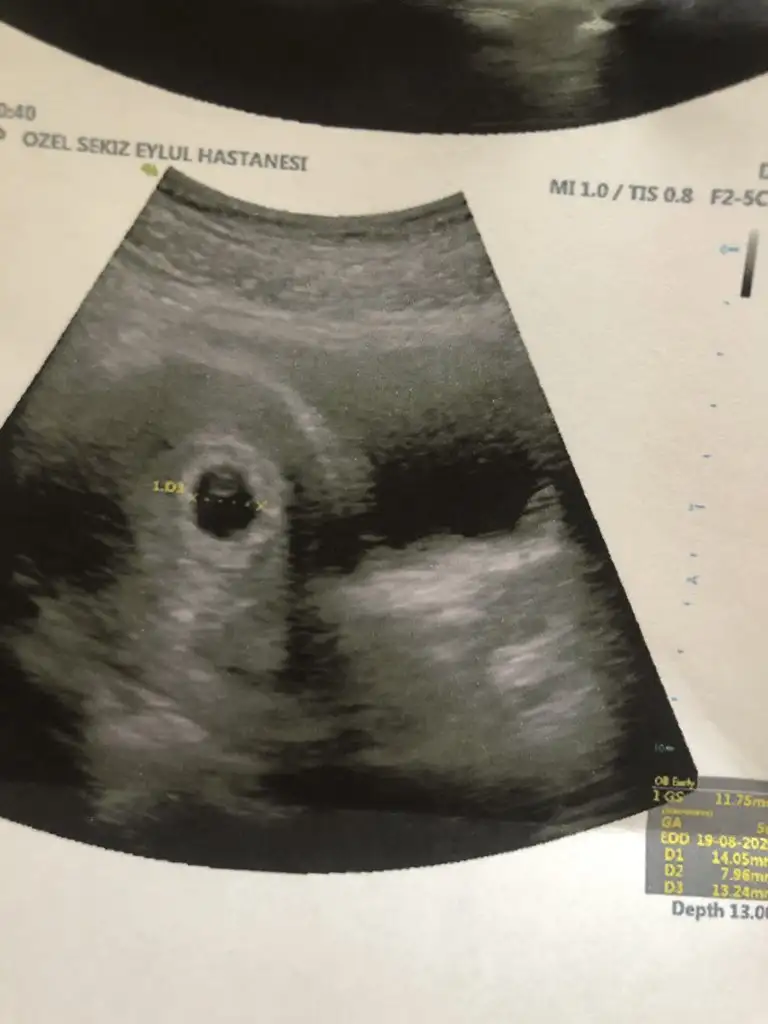

Hadi gözünüz aydın süper bir haber maşallah kaç haftalık

5+4 dedi canım. Uygulamalarda da aynı cıkıyor.

Kızlar kesemiz rahat gözüktü. Ama bebek konusunda öyle değil. Kese içinde beyaz bir şey var o bebek olabilir ama kesin değil dedi. Bebeğini gören arkadaşlarım var mı elinizde ultrason fotoğrafı?![]()

Canım benim 5+4 müş. İşte sadece keseyi net görebildik:)Yaaa masalllahhh bu goruntuyu ne zaman gorebılırım acaba:)